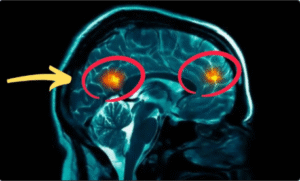

Last November, a 70-year-old minister collapsed during church service while the choir sang “How Great Thou Art”. His left side went cold, vision blurred, hand wouldn’t close – doctors called it a hypertensive crisis, a warning stroke that could kill in minutes.

How to Lower Blood Pressure for Seniors Over 60 High blood pressure means crushing headaches, pounding heart, ear ringing and fear of not waking up beside your spouse.